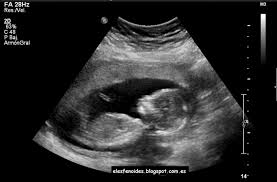

Se ha puesto en marcha recientemente una interesante iniciativa destinada a facilitar a las mujeres ciegas embarazadas conocer cómo es la cara de sus bebés antes de nacer, a través de impresiones realizadas en tres dimensiones. La propuesta se ha llevado a cabo en Brasil y ha contado con la participación de cuatro mujeres que pudieron percibir mediante el tacto el rostro de sus hijas/os.

Ecografía de un bebé